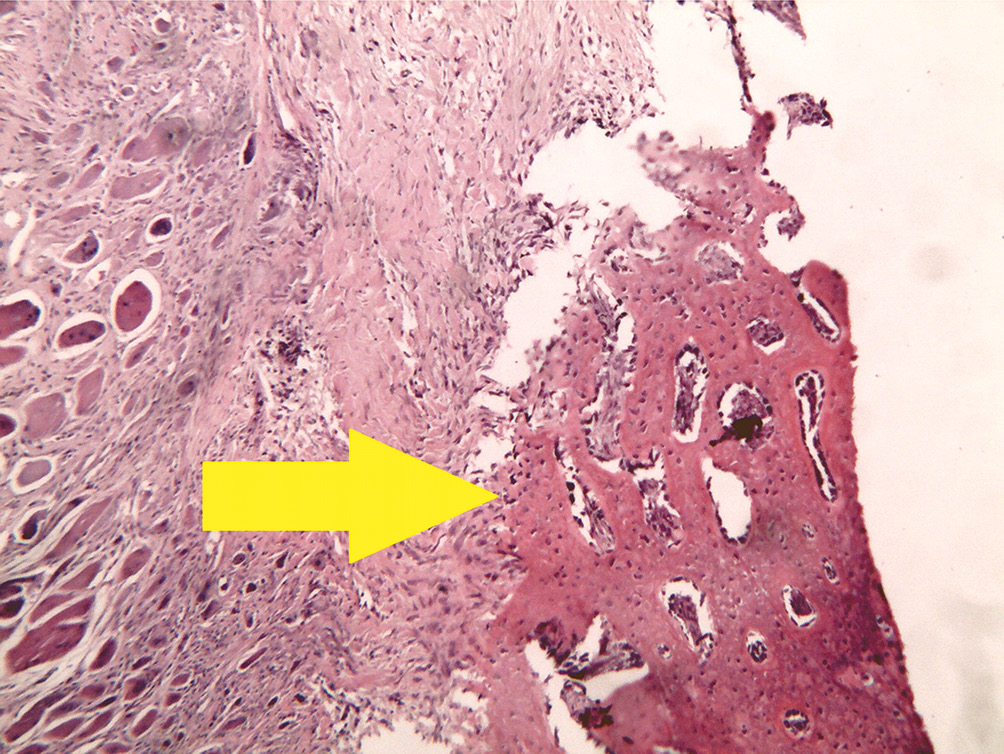

- Группа с губчатым материалом на основе хитозана (рис. 4).

Рис. 4. Группа с хитозаном: разрастание по краям дефекта ретикулофиброзной костной ткани. Окраска гематоксилином и эозином, увеличение ×40

На 28-е сутки в зоне дефекта отмечается участок, заполненный волокнистым хрящом. Элементов исследуемого образца синтетического материала в зоне дефекта не обнаружено. По краям дефекта кости виден переход волокнистой хрящевой ткани в ретикулофиброзную костную ткань.